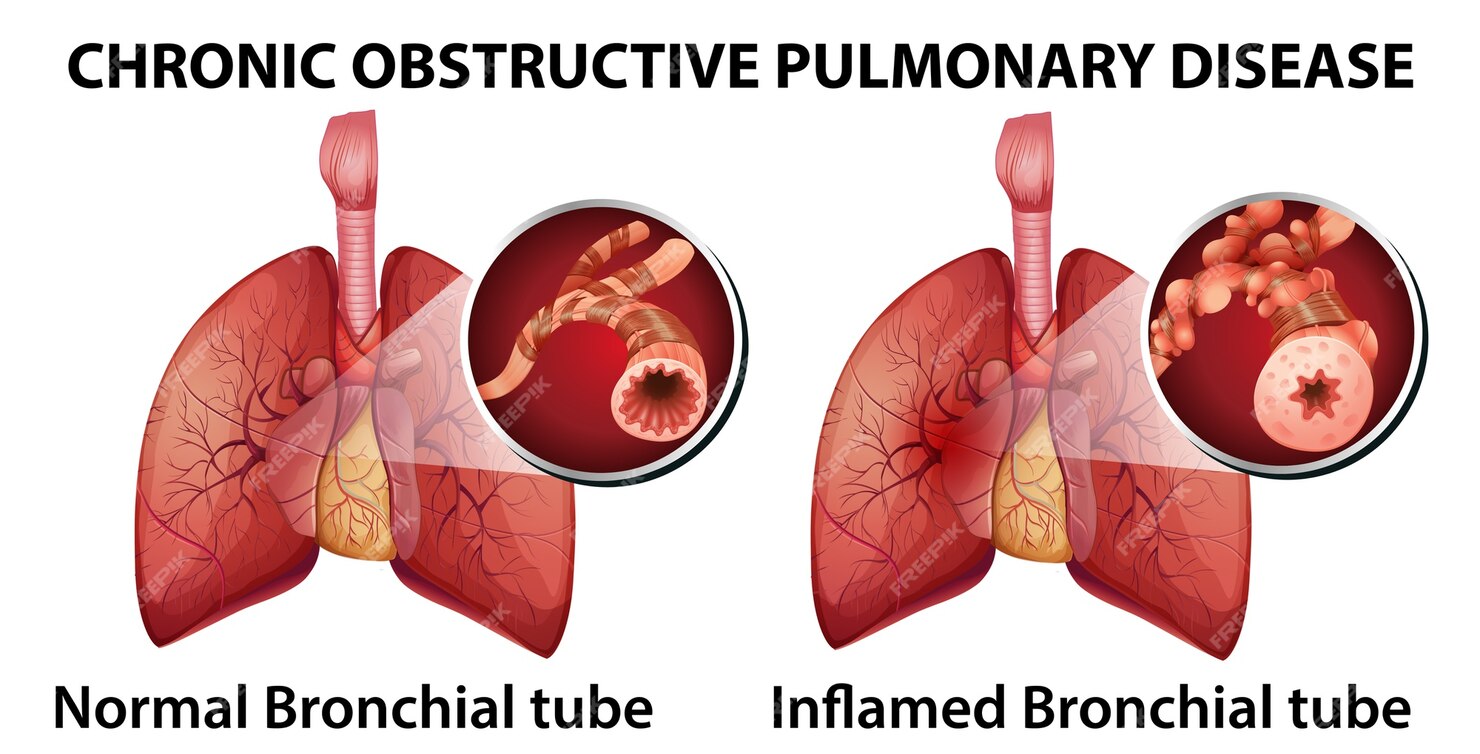

Doença pulmonar obstrutiva crônica Vetor Premium

DPOC (doença pulmonar obstrutiva crônica) é um conjunto de doenças respiratórias, como bronquite crônica e enfisema pulmonar, que bloqueiam as vias aéreas e dificultam a respiração. A principal causa da DPOC é o tabagismo, pois a fumaça e outras substâncias presentes no cigarro prejudicam o tecido das vias respiratórias, levando ao.

A doença pulmonar obstrutiva crônica (DPOC) caracteriza-se pela limitação crônica ao fluxo aéreo, não totalmente reversível, associada a uma resposta inflamatória anormal à inalação de partículas ou gases nocivos.

Poluição do ar intra e extradomiciliar. Na DPOC, ocorre inflamação crônica das vias aéreas centrais e periféricas, parênquima e vasos pulmonares em resposta à inalação de partículas e gases nocivos, com acúmulo principalmente de macrófagos, neutrófilos e linfócitos T (sobretudo CD8).